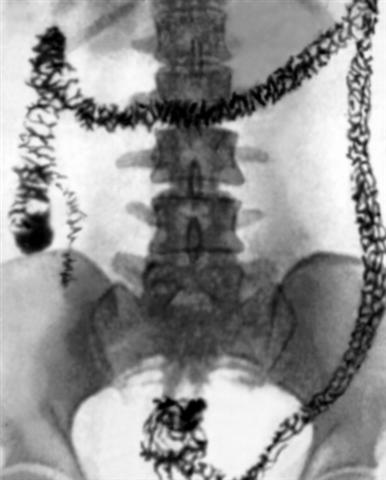

Рис. 1б). Обзорная рентгенограмма толстой кишки в норме после удаления из кишечника рентгеноконтрастной взвеси.